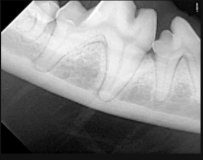

SOPIX är en DR sensor med kabel som kopplas i USB kontakten på er dator. Sensorn finns i storlekarna Size 1 (25x39mm) och Size 2 (31x42mm).

Size 1 är lämplig för katt och Size 2 för hund.

Sensorerna har en väldigt hög synbar upplösning tack vare en speciell fiberteknik, supersmå pixlar och känslig scintillator (lagret som omvandlar röntgen till elektronisk läsbart ljus). Pixlarna är endast 20um stora vilket ger en teoretisk upplösning på 25lp/mm. Kabeln är hela 370cm lång (70cm som inbyggd i Xmind Unity röntgenapparaten).